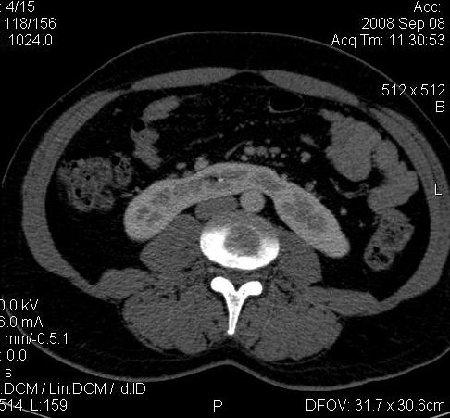

КТ Почек- подкова и уретеролитиаз

Данное наблюдение весьма демонстративно само по себе.

Ну ладно, раз никто больше не хочет, то отвечу свою версию - аномалия развития - подковообразная почка (horseshoe kidney).

Для невладеющего КТ,очень четка видна аномалия на 3-4х снимках.А вот на 4-м скане в проксим.сегменте цистоида тоже есть гиперденсное точечное образование-не камень случайно?